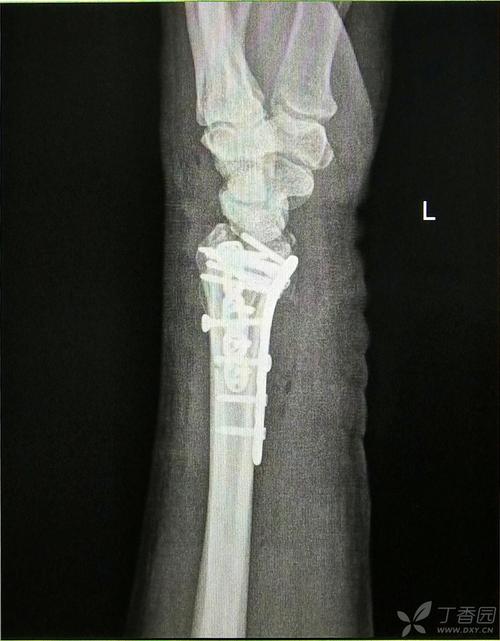

手桡骨远端骨折后遗症,桡骨远端骨折图片

黄骨头桡骨远端骨折手术日记——桡骨远端陈旧性粉碎性骨折一例 [病例

桡骨远端骨折图片

左桡骨远端骨折图片

右侧桡骨远端骨折图片

左手桡骨远端骨折图片

右手桡骨远端骨折图片

桡骨远端骨折钢板

桡骨远端骨折固定图片

正常桡骨远端骨折图片

桡骨远端骨折复位图片